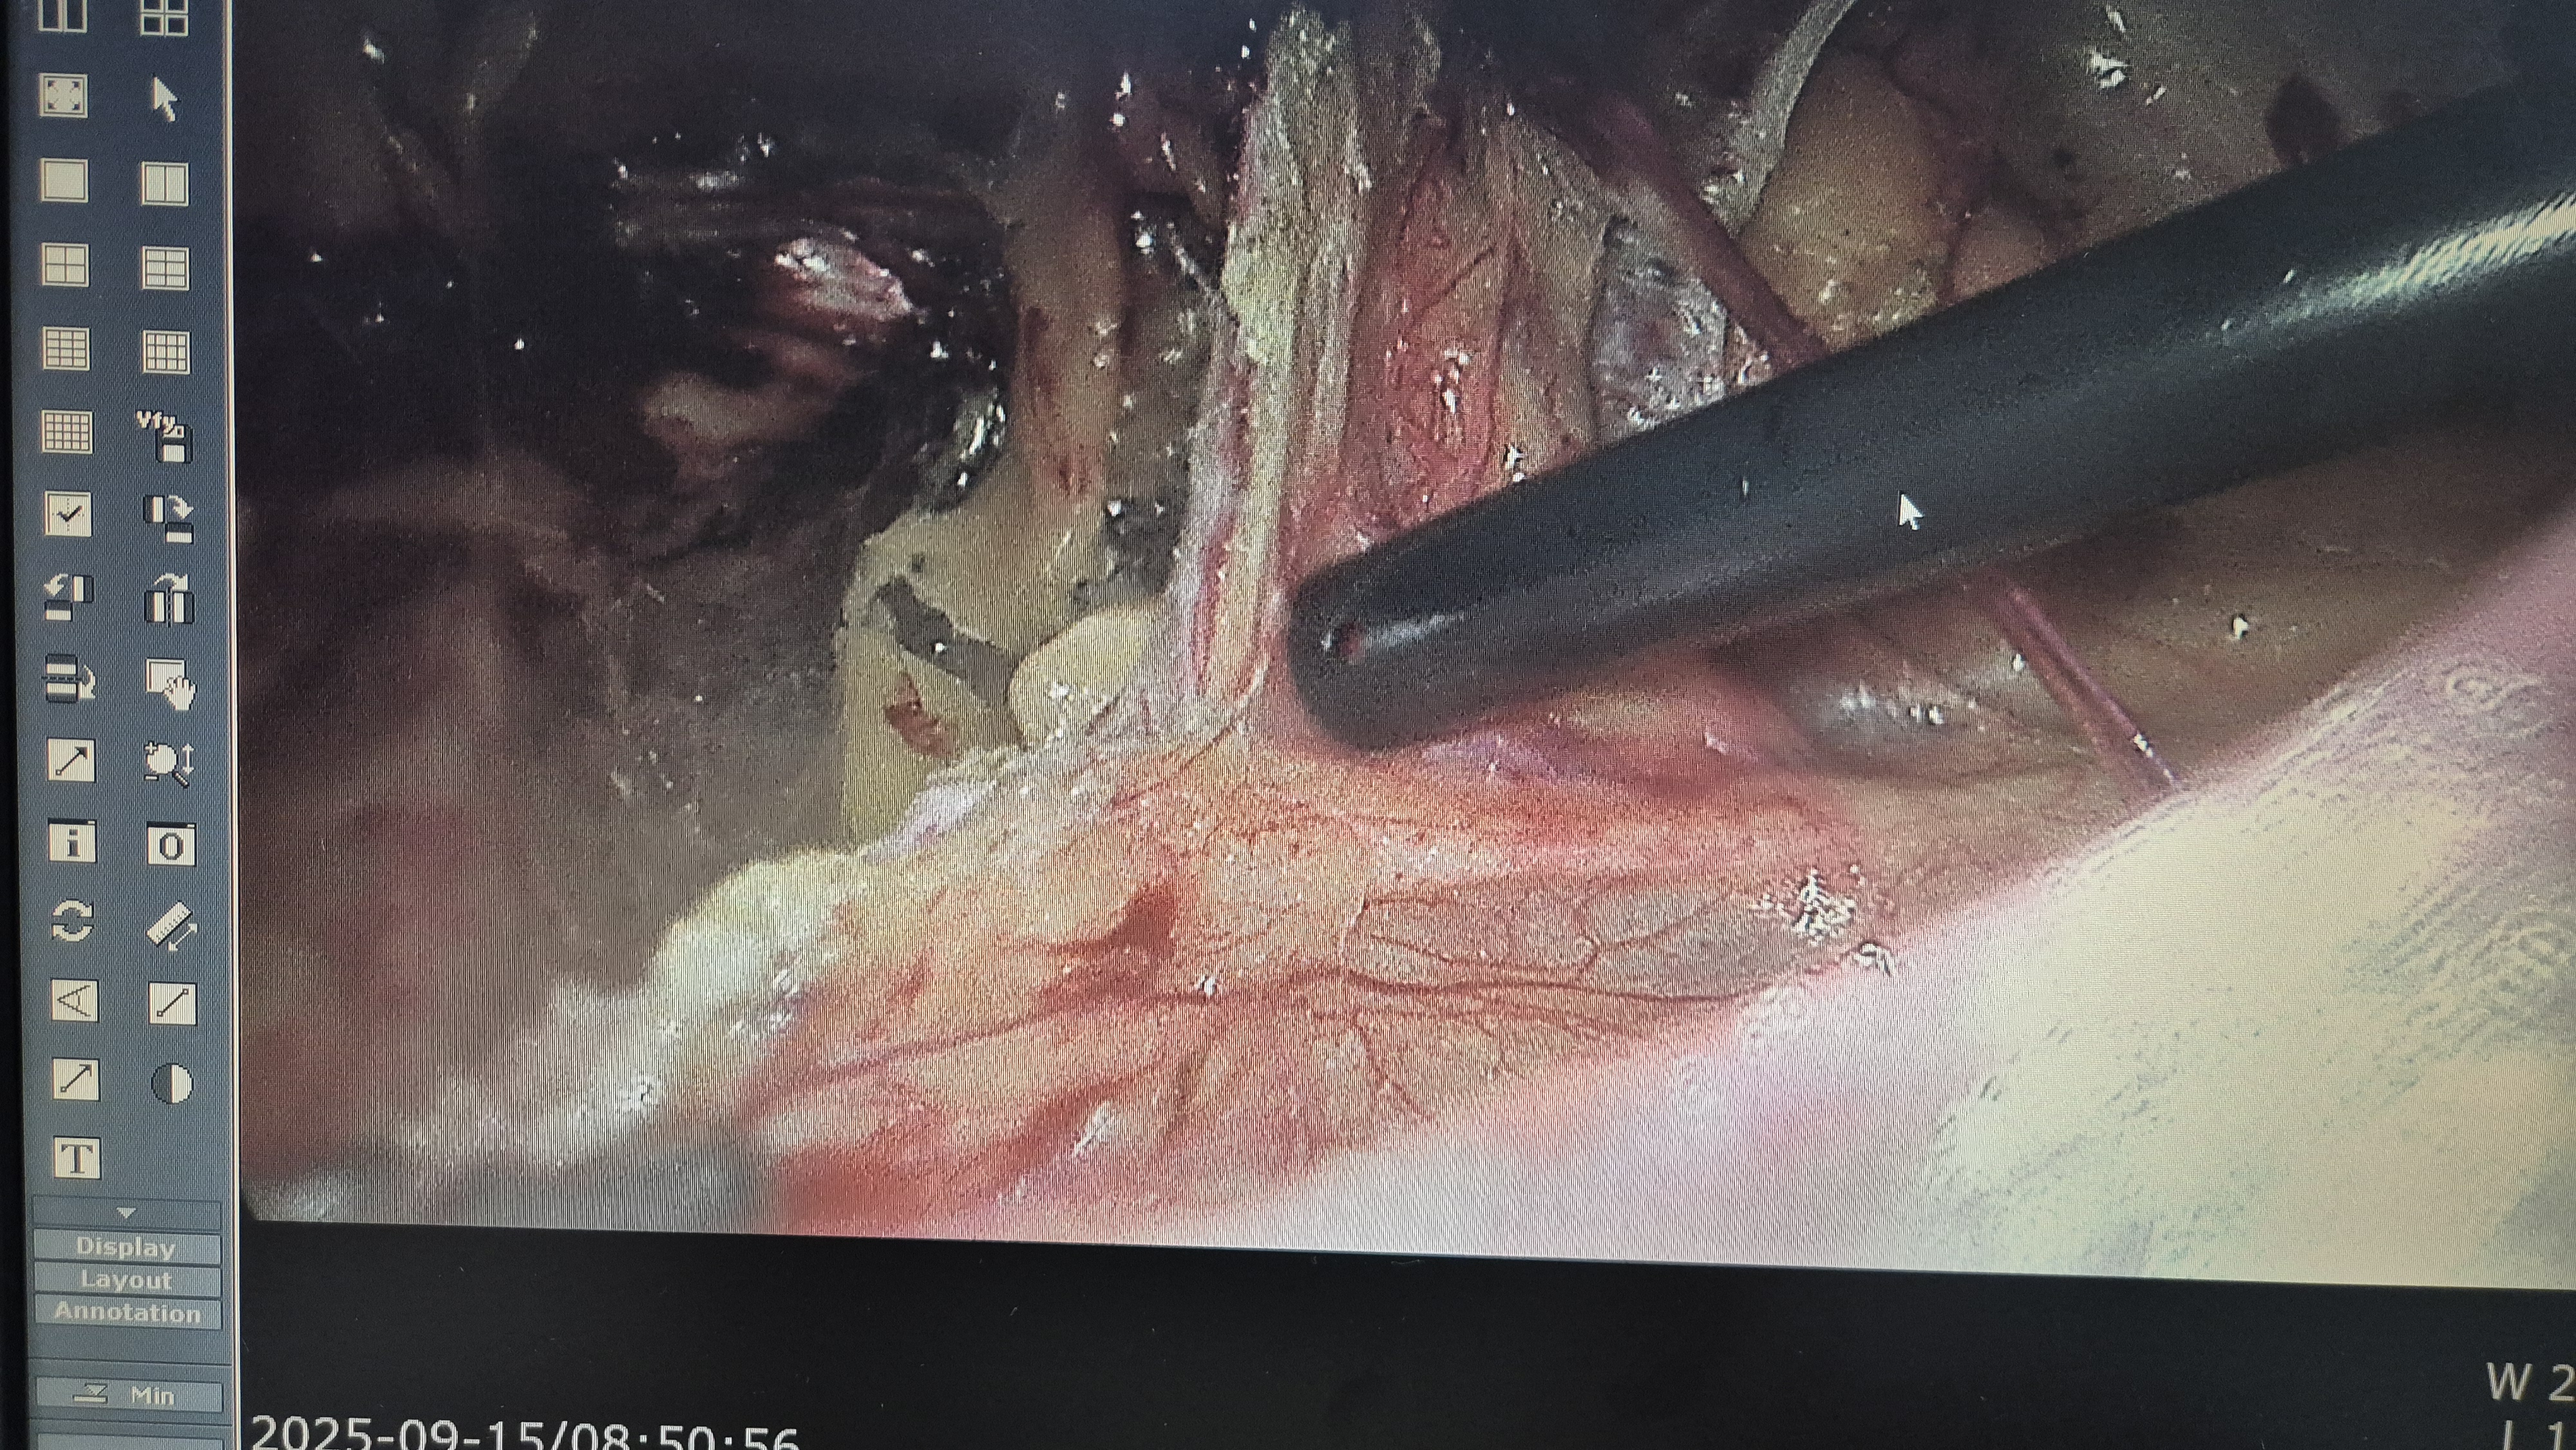

탈장 확인후.

박리.